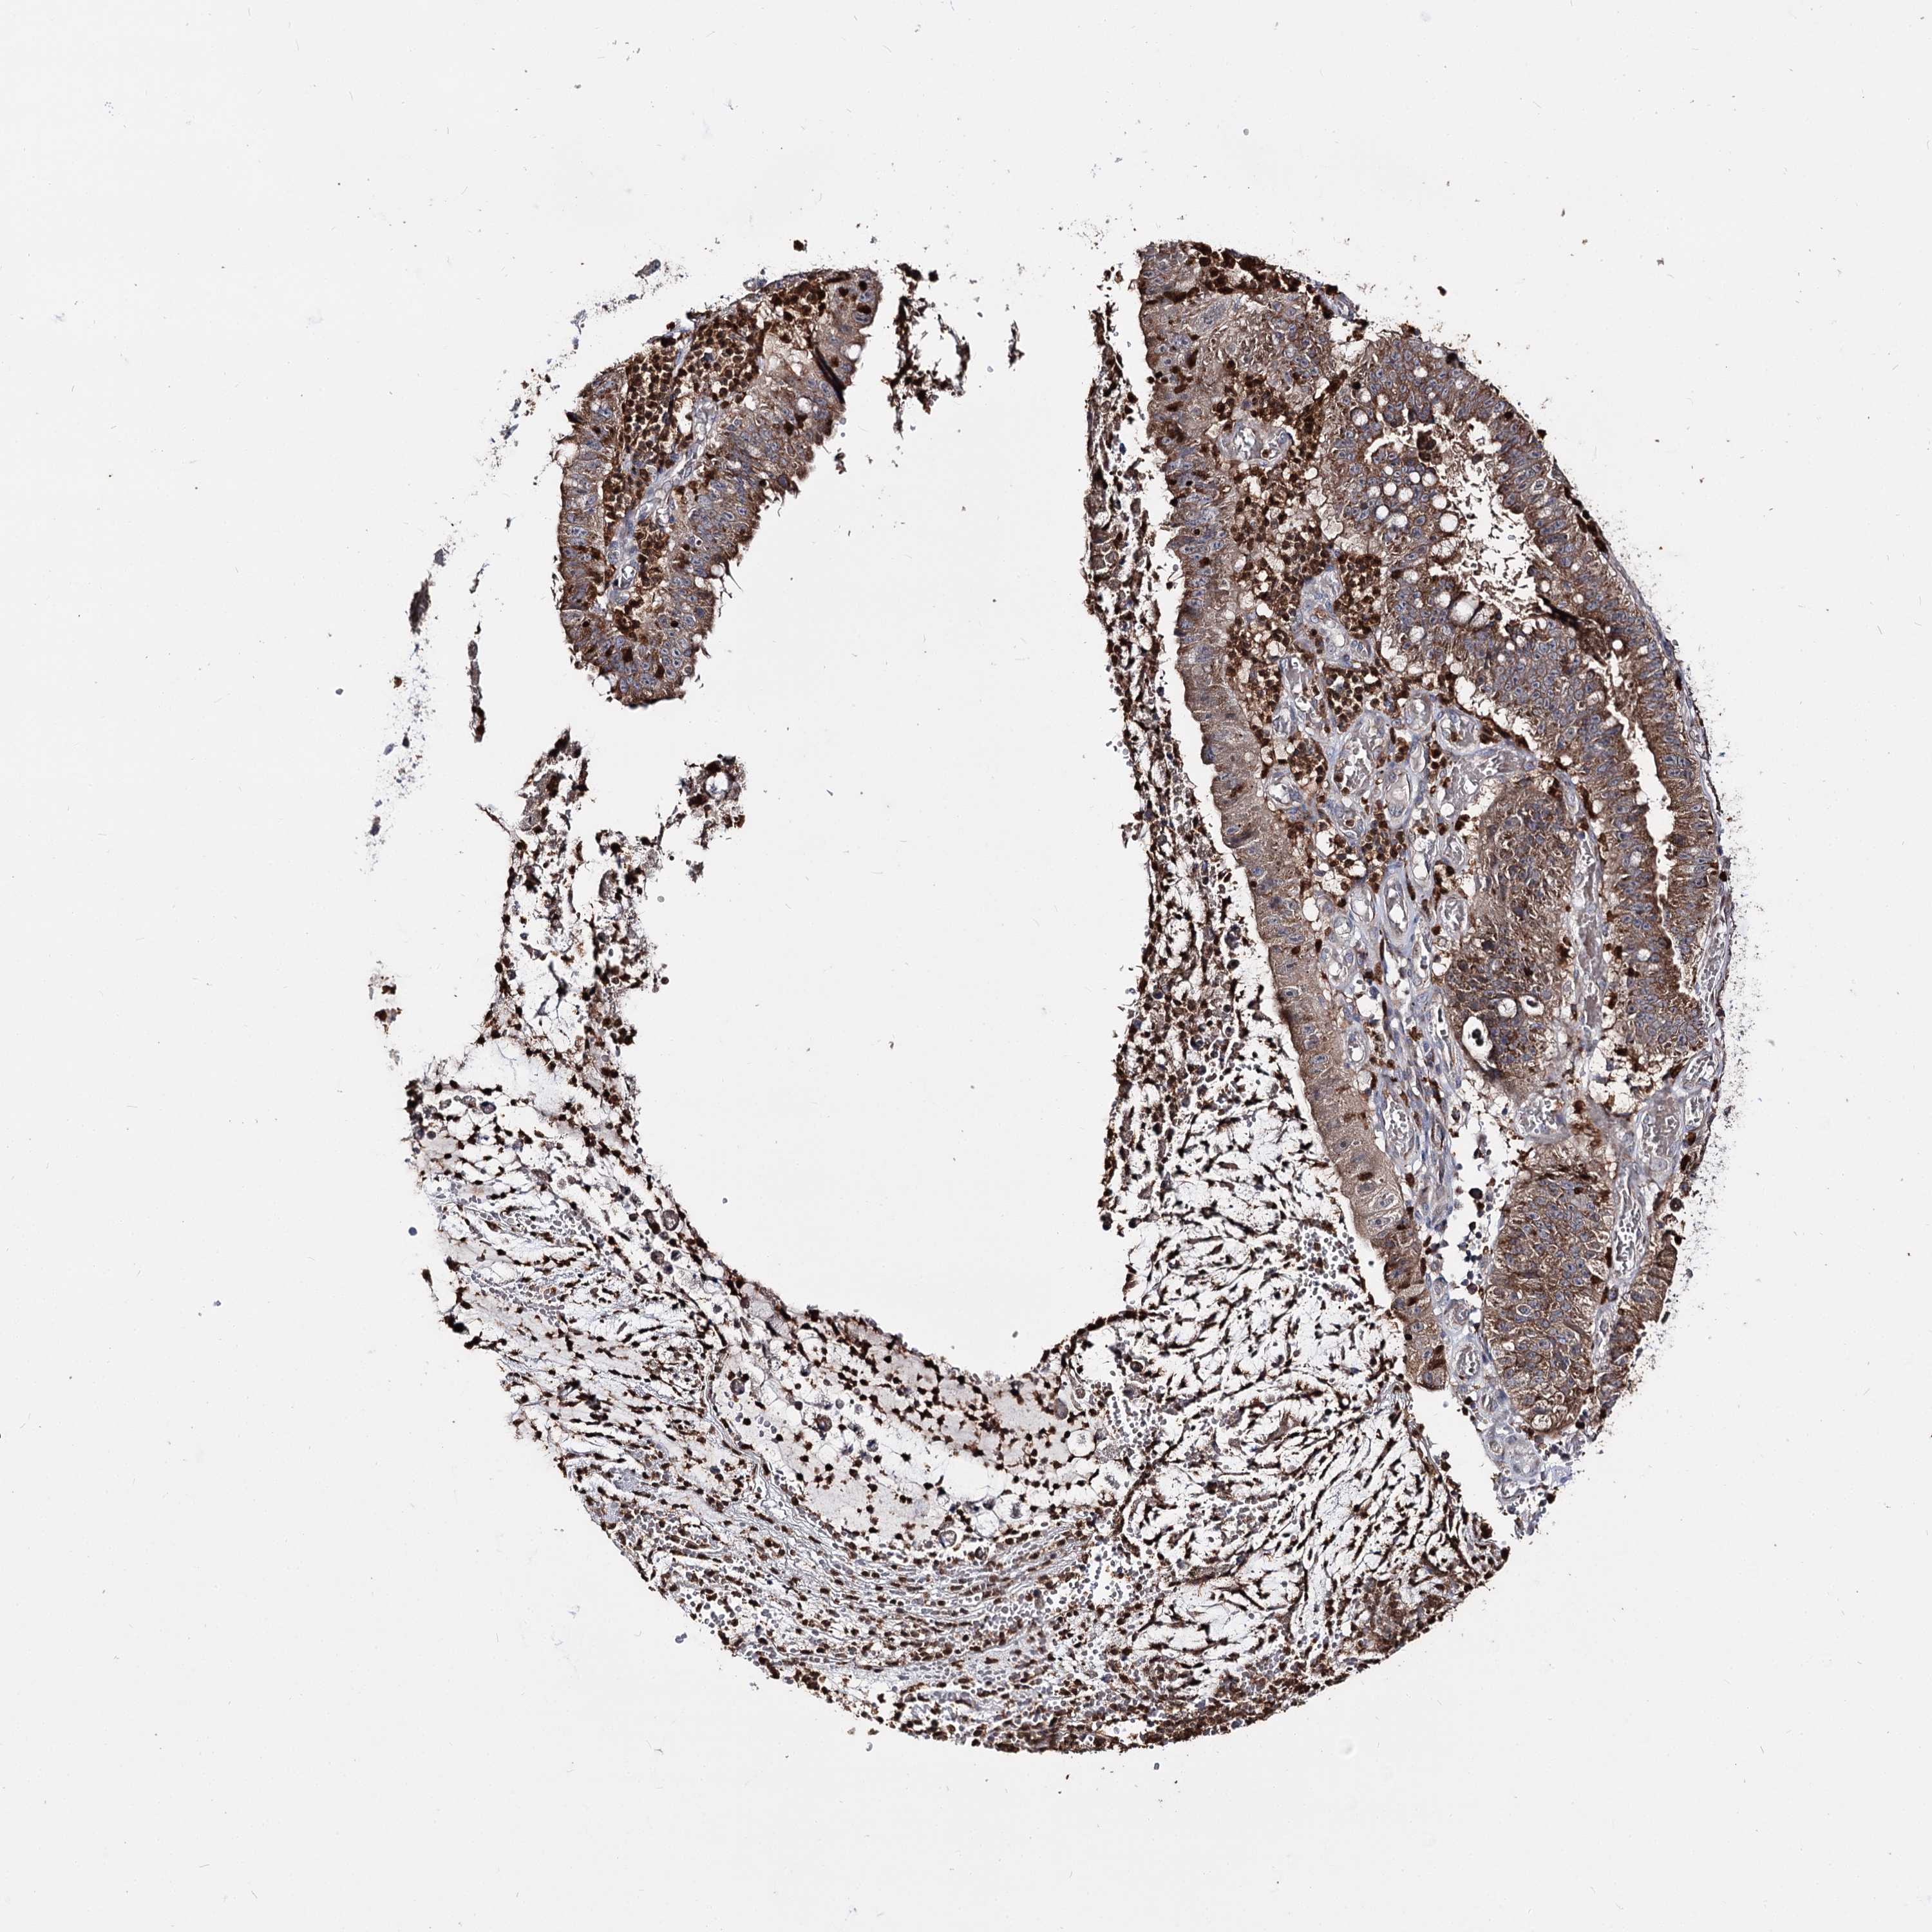

STOMACH CANCER - Protein expressioni

A mouse-over function shows sample information and annotation data. Click on an image to view it in a full screen mode. Samples can be filtered based on level of antibody staining by selecting one or several of the following categories: high, medium, low and not detected. The assay and annotation is described here.

Note that samples used for immunohistochemistry by the Human Protein Atlas do not correspond to samples in the TCGA dataset.

Antibody stainingi

Antibody staining in the annotated cell types in the current human tissue is reported as not detected, low, medium, or high, based on conventional immunohistochemistry profiling in selected tissues. This score is based on the combination of the staining intensity and fraction of stained cells.

Each image is clickable and will lead to virtual microscopy that enables deeper exploration of all samples and also displays staining intensity scores, fraction scores and subcellular localization as well as patient and tissue information for each sample.

Antibody HPA038040

Staining

High

Medium

Low

Not detected

Intensity

Strong

Moderate

Weak

Negative

Quantity

>75%

75%-25%

<25%

None

Location

Nuclear

Cytoplasmic/membranous

Cytoplasmic/membranous,nuclear

Adenocarcinoma, NOS

Adenocarcinoma, High grade